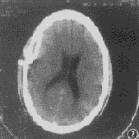

此病易和脑脓肿、脑膜炎相混淆,最好进行脑血管造影和脑CT扫描,可见占位脓肿及半球受压血管影区。